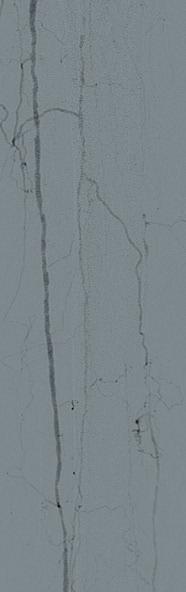

THE PATIENT IS AN 81-YEAR-OLD man with a past medical history of hypertension, hyperlipoproteinaemia, and remote history of smoking, who presents with an expanding saccular abdominal aortic aneurysm (AAA) and severe hip claudication. A preoperative computed tomography angiography (CTA) reveals dense circumferential calcified 90% stenosis of the bilateral common iliac arteries (Figures 1 and 2). In addition, the patient had a mid-aortic highly calcified stenosis. The patient desired a minimally invasive approach and given the underlying conditions, an EVAR was the best option to treat the AAA, as well as the bilateral common iliac artery stenosis.

Preoperative planning focused on three main areas of concern: the first is whether or not the stent graft could advance through the iliacs; secondly, would the stent graft limbs open to nominal diameter within the iliacs; and lastly, whether or not the stent graft would open fully within the AAA.

We used a percutaneous approach. Initially, we were unable to advance the 16Fr DrySeal sheath for the main graft on the right or the 12Fr DrySeal sheath on the left side for the contralateral limb (Figure 3). At this point, we performed IVL with a 7.0x60mm IVL catheter, of both the right and left common iliac arteries. We delivered 150 pulses to each vessel at 4atm and subsequently carefully dilated to nominal pressure of 6atm. Both arteries dilated easily. The Gore Excluder graft was delivered, and the limbs were placed within the common iliac arteries. Post-implantation balloon angioplasty was completed and revealed complete seal of the AAA and no residual stenosis in the iliacs (Figure 4). The patient was found to have a 90% stenosis of the left renal artery, which was treated with a balloon-expandable stent. His postprocedural CT scan revealed a very nice result, a sealed AAA, wide iliac arteries, and no residual stenosis.

Figure 3. Initial intraoperative angiogram

Figure 1. Preoperative CTA revealing dense calcified stenosis of the iliac bifurcation

Figure 4. Completion arteriogram, areas of stenosis completely resolved

Figure

common iliac luminal diameter of 3mm, left common iliac diameter of 5mm